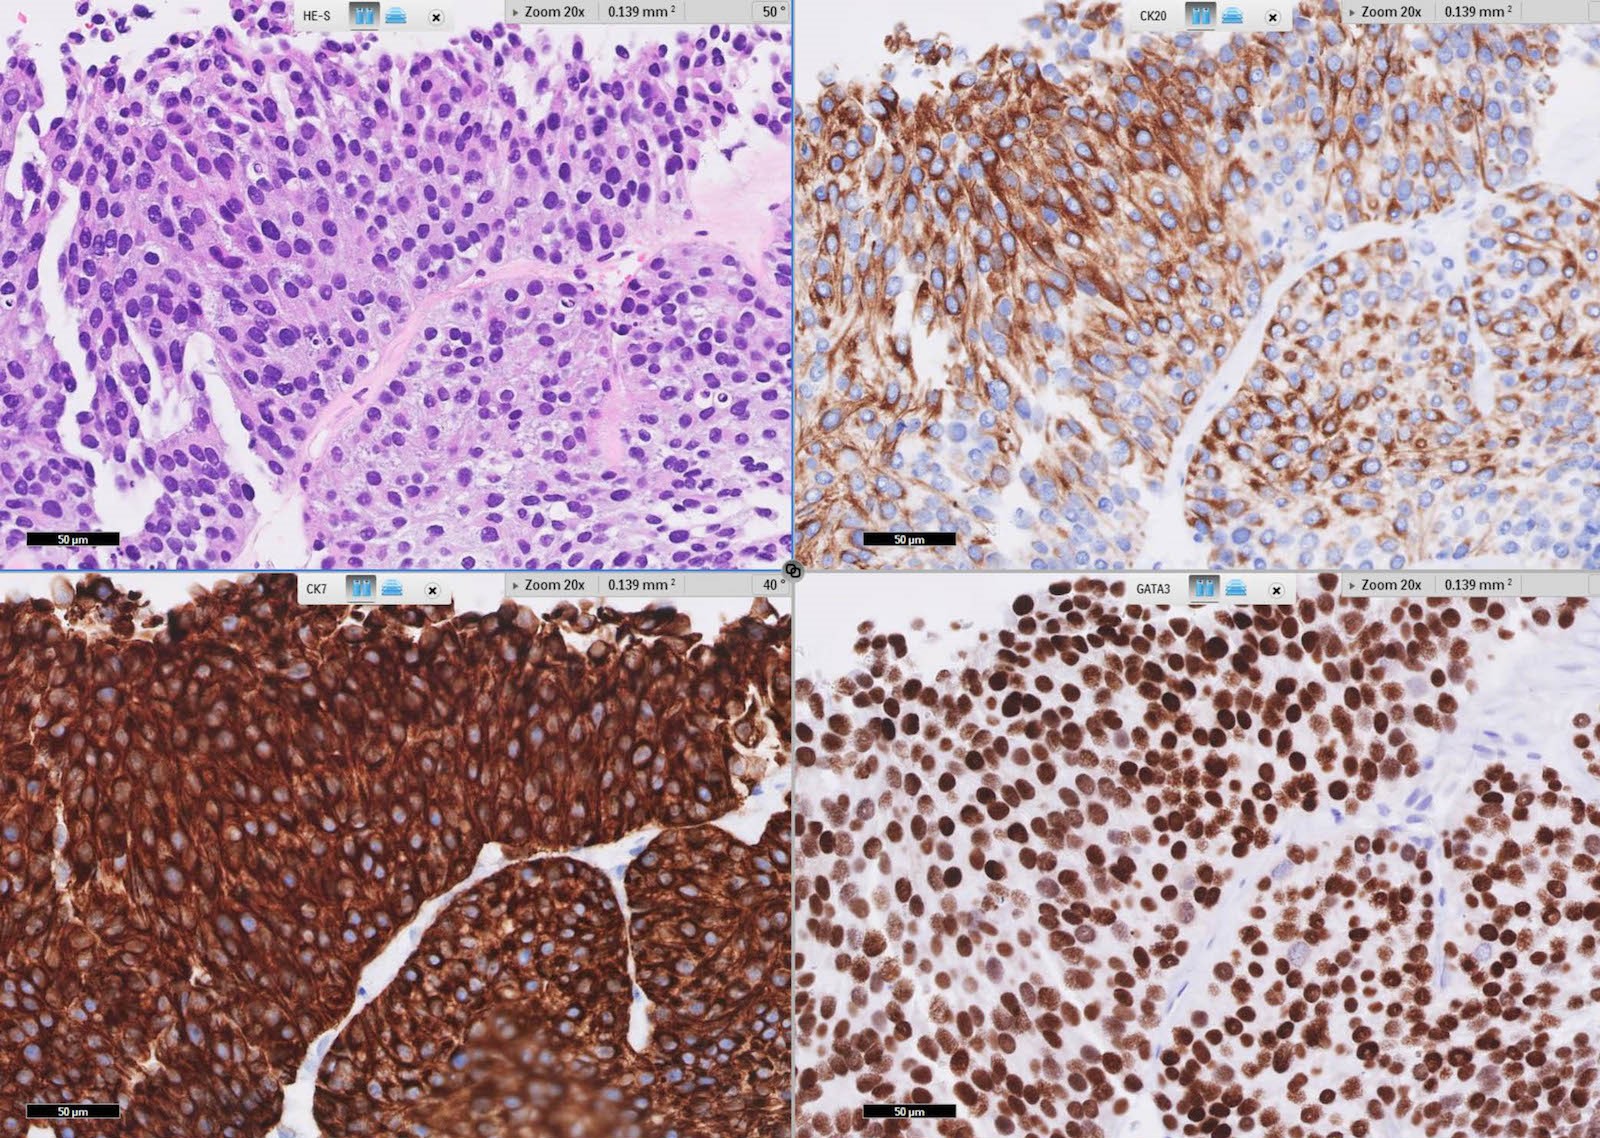

Microscopic (histologic) images

Contributed by Emily S. Reisenbichler, M.D., Andrey Bychkov, M.D., Ph.D., Maria Tretiakova, M.D., Ph.D. and Debra Zynger, M.D.

Positive staining - tumors

- Breast cancer, invasive (72 - 94%) (Mod Pathol 2010;23:654, Am J Clin Pathol 2012;138:57), well differentiated > poorly differentiated; more sensitive than GCDFP-15 and mammoglobin in staining of metastatic breast carcinoma (Ann Diagn Pathol 2015;19:6)

- Primary and metastatic urothelial carcinoma (67 - 93%) (Am J Surg Pathol 2007;31:673, Am J Surg Pathol 2013;37:1876)